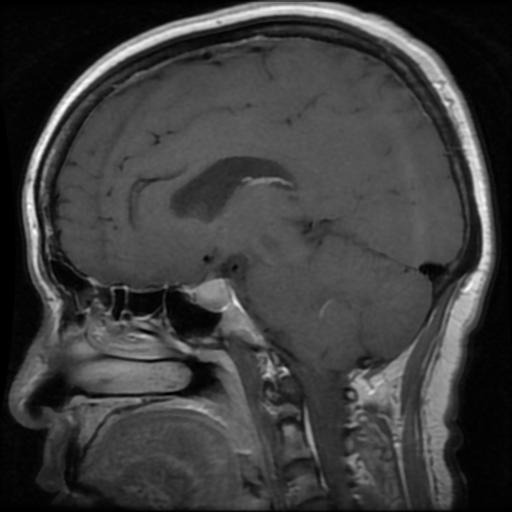

Refer to caption

Figure 1: MRI Scans Showing Various Conditions: Glioma, Meningioma,a Non-Tumor Case and Pituitary Tumor

A few images from each class were visually inspected to understand dataset balance and quality, with examples shown in Figure 1. The varying nature of gliomas, meningiomas, pituitary tumors, and non-tumor cases hence brought a firm rationale before the model building and evaluating stages.